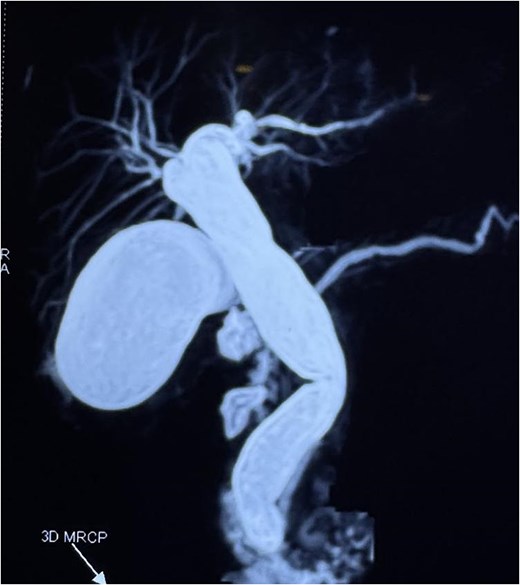

A computed tomography scan confirmed the presence of a duodenal diverticulum (3 cm) in the second part of the duodenum, localized perforation of the gallbladder fundus, and extrahepatic bile duct dilation (Fig. 1). Magnetic resonance cholangiopancreatogram further characterized the findings, revealing biliary stasis secondary to the periampullary diverticulum (Lemmel’s syndrome) without any structural distal obstruction (Fig. 2). Upper gastrointestinal endoscopy excluded periampullary malignancy and confirmed biliary stasis due to the periampullary diverticulum (Fig. 3).

Contrast-enhanced CT scan demonstrating (A) localized perforation at the fundus of gallbladder (white arrow). (B) Extrahepatic biliary tract dilatation (big arrow); a periampullary duodenal diverticulum (small arrow).

Magnetic resonance cholangiopancreatogram (MRCP) showing biliary stasis without any structural distal obstruction.